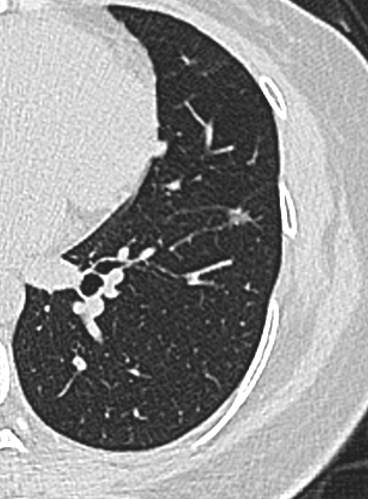

21年底左下肺,直径5.2mm:

img